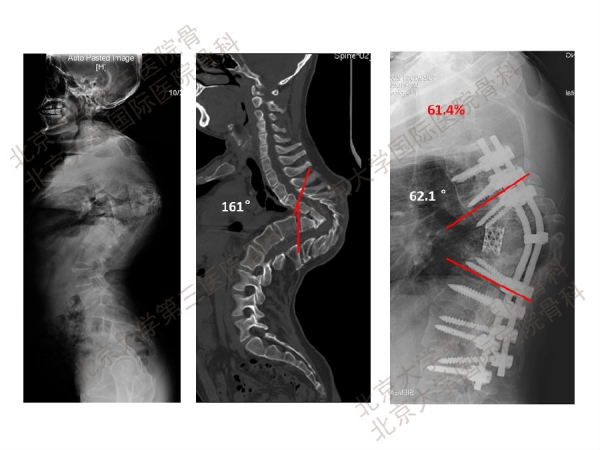

如今,脊柱截骨术因其可以取得很好的矫正效果,临床应用越来越广泛。但是,脊柱截骨手术并风险大、并发症高,脊柱外科医生应予以高度重视,在临床上必须严格掌握适应证。脊柱截骨矫形手术容易出现硬膜破损、神经根损伤、脊髓损伤、胸膜损伤等等并发症。其中,术中及术后早期出现的神经并发症更是不容忽视。

陈仲强教授指出,这可能与截骨过程手术操作的震动、手术操作对脊髓的直接损伤、矫正畸形时截骨断端错动、矫形导致脊髓过度短缩或拉伸、脊髓血供减弱或障碍、内置物或植骨块移位压迫脊髓、术后伤口深部血肿压迫脊髓,以及其他不明原因有关。